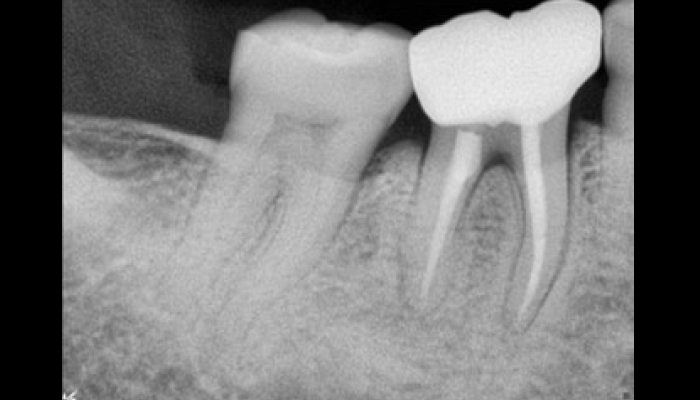

턱관절 머리뼈와 아래턱 사이에 있는 관절을 말합니다. 이러한 관절원판이 정상위치에서 있지 않거나, 마모되었을 때 턱관절 디스크가 발생하게 됩니다.

• 01 치아 교합 문제

치아가 잘 맞지 않거나,구강내 질환에 의해 턱관절의 운동에 이상이 생기면, 턱관절에 악영향이 가해집니다.